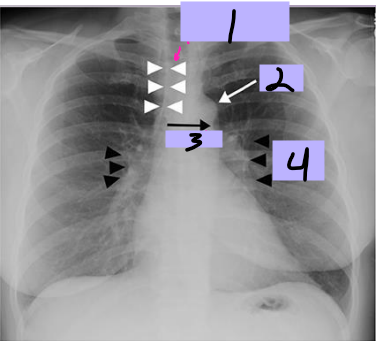

Aortic arch

#1

Superior vena cava

#2

Right pulmonary artery

#3

Right descending pulmonary artery

#4

Right atrium

#5

Right ventricle

#6

Left pulmonary artery

#7

Descending aorta

#8

Left ventricle

#9

Inferior vena cava

#10

Paratracheal stripe

#1

Aortic knob

#2

AP window

#3

Hila

#4